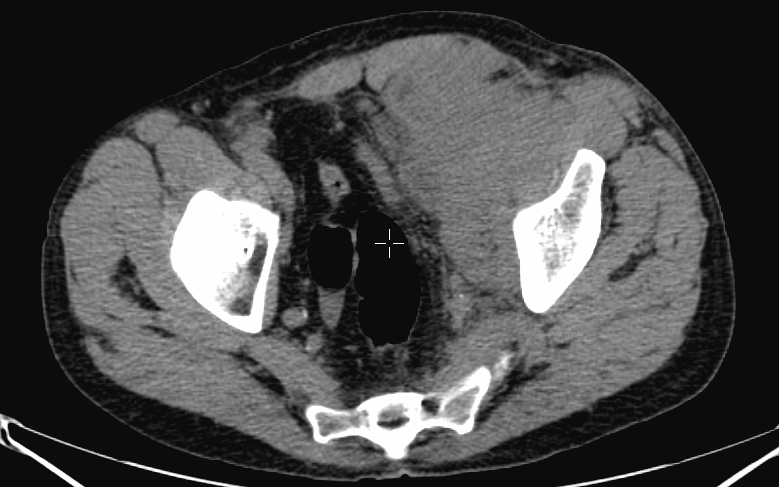

The most common clinical use of FDG-PET is in the form of whole-body scan, with oncologic indications. The majority of malignant tumors operate with higher energy consumption and show an increased glucose metabolism, consequently an increased uptake of FDG. The grade of malignancy is usually proportional to the rate of uptake. This method is useful in oncologic diagnostics, since it is capable to differentiate benign lesions from malignant ones. Whole-body PET imaging is capable to detect the primary tumor with local nodal metastases as well as distant metastatic lesions (staging) in one examination. (Figure 10.)

10. Ewing’s sarcoma in the right humerus. Staging FDG PET-CT. PET Maximum Intensity Projection (MIP) image (a), transversal (b,c) and coronal (d) plane fused PET-CT images. Multiplex metastatic process with nodal, lung and bone involvement.

In the staging of malignant diseases FDG-PET is extremely important, since it has a greater sensitivity and specificity than the morphologic imaging modalities.